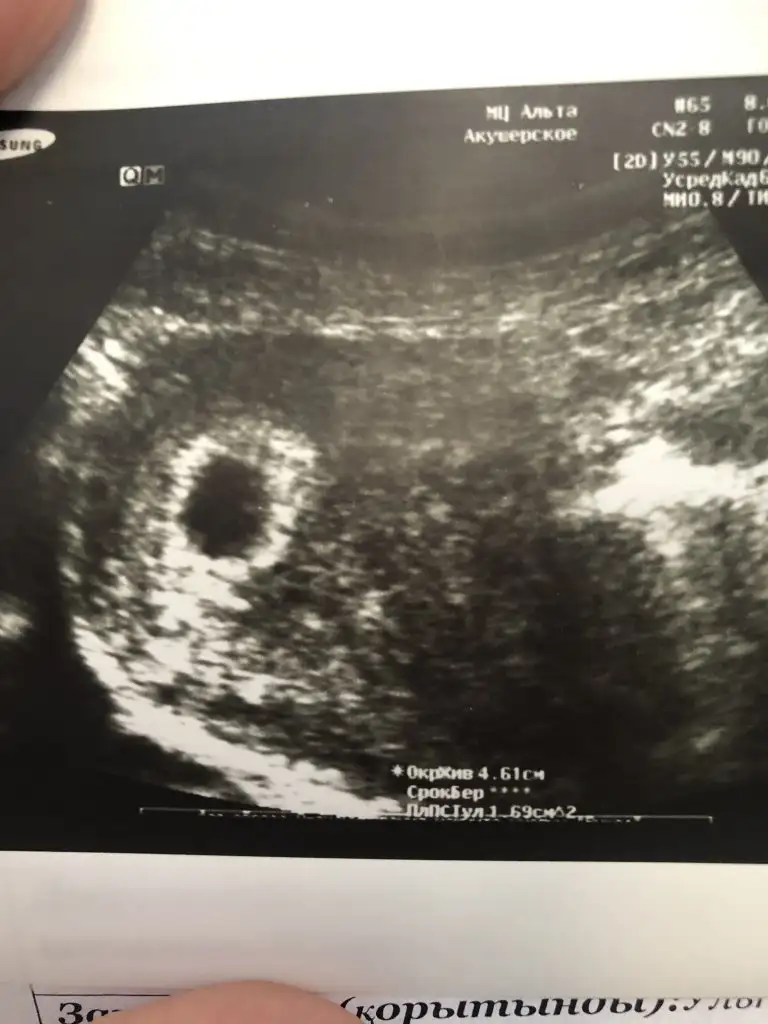

Kızımız da kaçtı şu an oğlunuz da kaç onu da belirtir misinizIkili tarama testi sonucunda free beta hcg (fbhcg) degeri 50 nin alti olursa erkek 50 uzeri olursa kız olma ihtimali daha yuksek oluyormus bu tur seyler okudum ne kadar dogru bilmiyorum ama kizimda 50 uzeriymis bu sefer 50 altinda dr erkek diyor bakalim

Kızımda 51 miş simdi 28 cikmisKızımız da kaçtı şu an oğlunuz da kaç onu da belirtir misiniz

Benim 45 tam sinirKızımda 51 miş simdi 28 cikmis

Benim 45 tam sinir